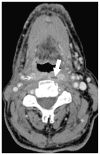

Cross-sectional imaging plays an important role in the evaluation of the retropharyngeal space (RPS) and the prevertebral space (PVS). Because of their deep location within the neck, lesions arising within these spaces are difficult, if not impossible, to evaluate on clinical examination. This article details the cross-sectional anatomy and imaging appearances of primary and secondary diseases involving the RPS and PVS, including metastasis and spread from adjacent spaces. The role of image-guided biopsy is also discussed.